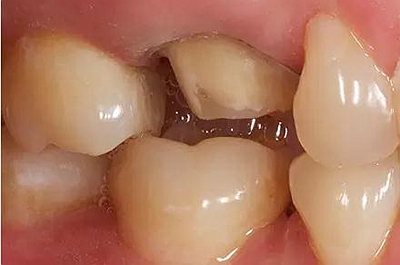

咬合間距

與對牙合牙的咬牙合面間隙至少保留: 1.0 mm 點隙裂溝處的距離,1.5 mm 牙尖高度的距離。